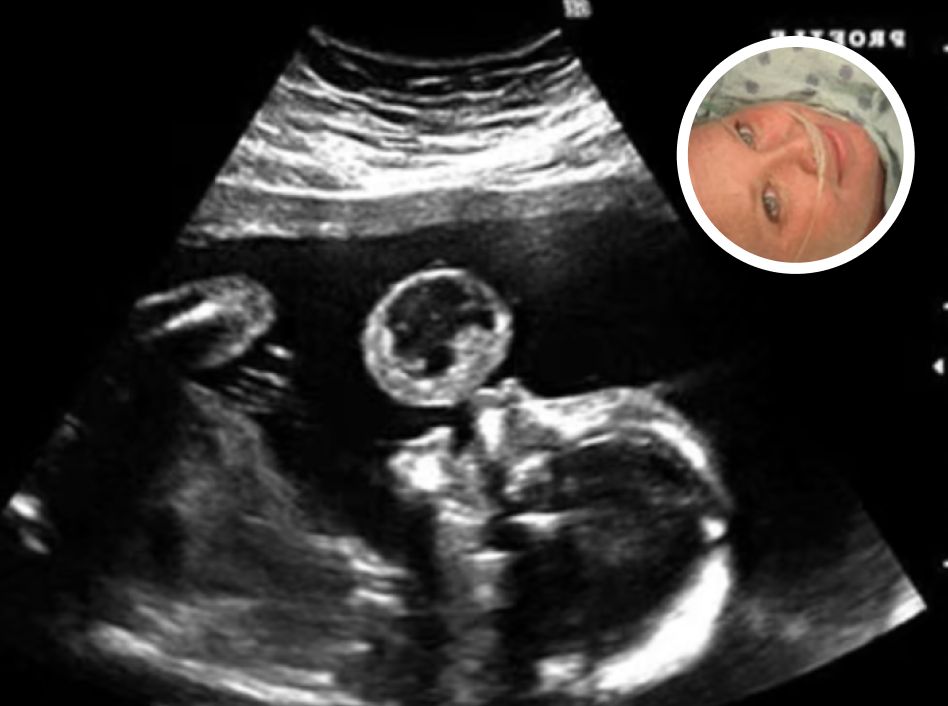

Tammy Gonzalez, a Miami resident, was expecting her baby when she went in for a standard ultrasound—a moment many mothers anticipate with joy, as they catch the first glimpse of their child. But during this appointment, doctors noticed something alarming. Hovering just above the baby’s mouth was what appeared to be a large, translucent bubble.

After further analysis, the bubble was diagnosed as a teratoma—a rare and often life-threatening tumor that can develop in utero. These tumors are seen in approximately 1 in every 100,000 births and can grow rapidly, threatening the baby’s ability to survive. The news was devastating. Doctors warned Gonzalez of the risks: not only could the tumor lead to miscarriage, but continuing the pregnancy could also endanger her own health. The medical recommendation was clear—termination.

The procedure was led by Dr. Ruben Quintero, director of the Fetal Therapy Center at Jackson Memorial Hospital in Miami, who agreed to attempt the groundbreaking surgery. Using a quarter-inch incision, he threaded a small endoscopic camera and precise surgical instruments through Gonzalez’s abdomen and into the amniotic sac, allowing him to visualize the tumor in real time.

With the camera showing a close-up of the tumor, Dr. Quintero made a critical decision. Using tiny tools, he severed the tumor’s stem. The moment the tumor detached, it floated away from the baby’s face, its danger neutralized.

“It was a decisive moment,” Dr. Quintero later recalled. “We went ahead and cut the stem, and sure enough, the tumor fell right out.”

Because the tumor was too large to remove safely through the incision, it was left inside the womb, floating in the amniotic fluid. Over the next four months, as Gonzalez carried her daughter to term, the tumor continued to shrinknaturally.